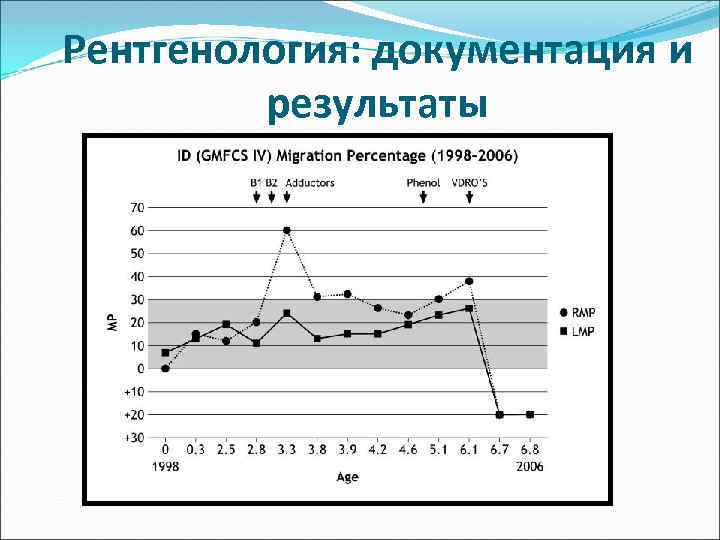

Рентгенология: документация и результаты